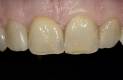

Das Ziel ist eine funktionell und ästhetisch perfekte Versorgung, die sich harmonisch in das bestehende Gebiss einfügt – für langfristige Stabilität, Sicherheit und ein natürliches Gefühl beim Kauen und Sprechen.